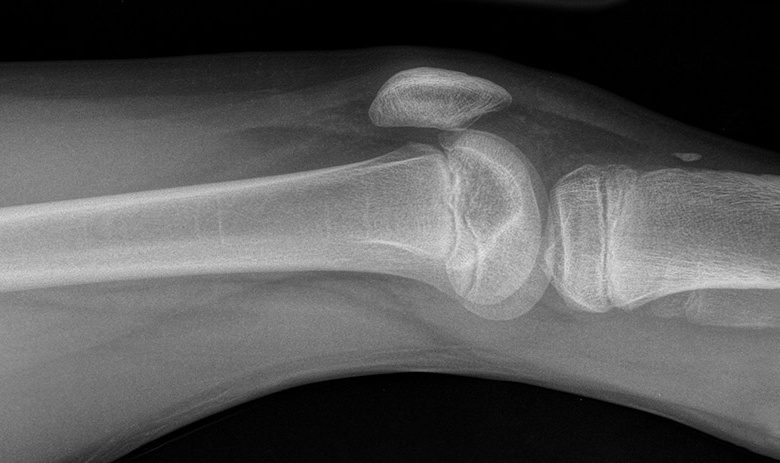

Фото: radiopaedia.org

Компания «НЭВЗ-Керамикс» провела испытания новой конструкции керамического эндопротеза коленного сустава. Разработка может прослужить не менее 10 лет.

Новинка представляет собой симбиоз из современных международных решений в области протезирования. Её особенностью являются суставные поверхности, выполненные из биостабильного керамического матрикса, который не подвержен коррозии и не отторгается организмом.

Испытания были проведены в соответствии с требованиями международных стандартов ISO. Протез повторил поведение реального сустава с ужесточением прилагаемой нагрузки. Разработка выдержала пять миллионов циклических изменений угла сгибания и разгибания.

В процессе испытаний сустав сохранил стабильность конструкций, целостность всех компонентов не нарушилась. Текущий анализ результатов тестов подтвердил работоспособность протеза, сообщает РИА Новости.